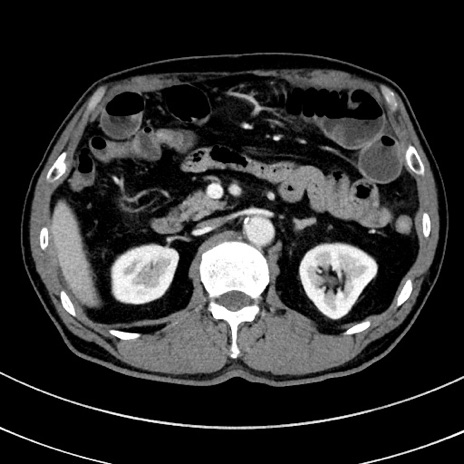

症例8(横断像)

【症例】 60歳代男性

【主訴】 黒色吐物

【現病歴】 4日前から嘔気自覚、2日前の朝食後にも嘔気あり、自分で手で嘔吐反射起こし嘔吐したところ血が混ざっていたため受診。

【既往歴】 5年前汎発性腹膜炎を伴う急性虫垂炎で手術、高血圧、前立腺肥大症、高脂血症

【身体所見】 腹部正中に手術癩痕あり 腹部平坦・軟圧痛なし膨満感あり

【データ】WBC 8400、CRP 4.54